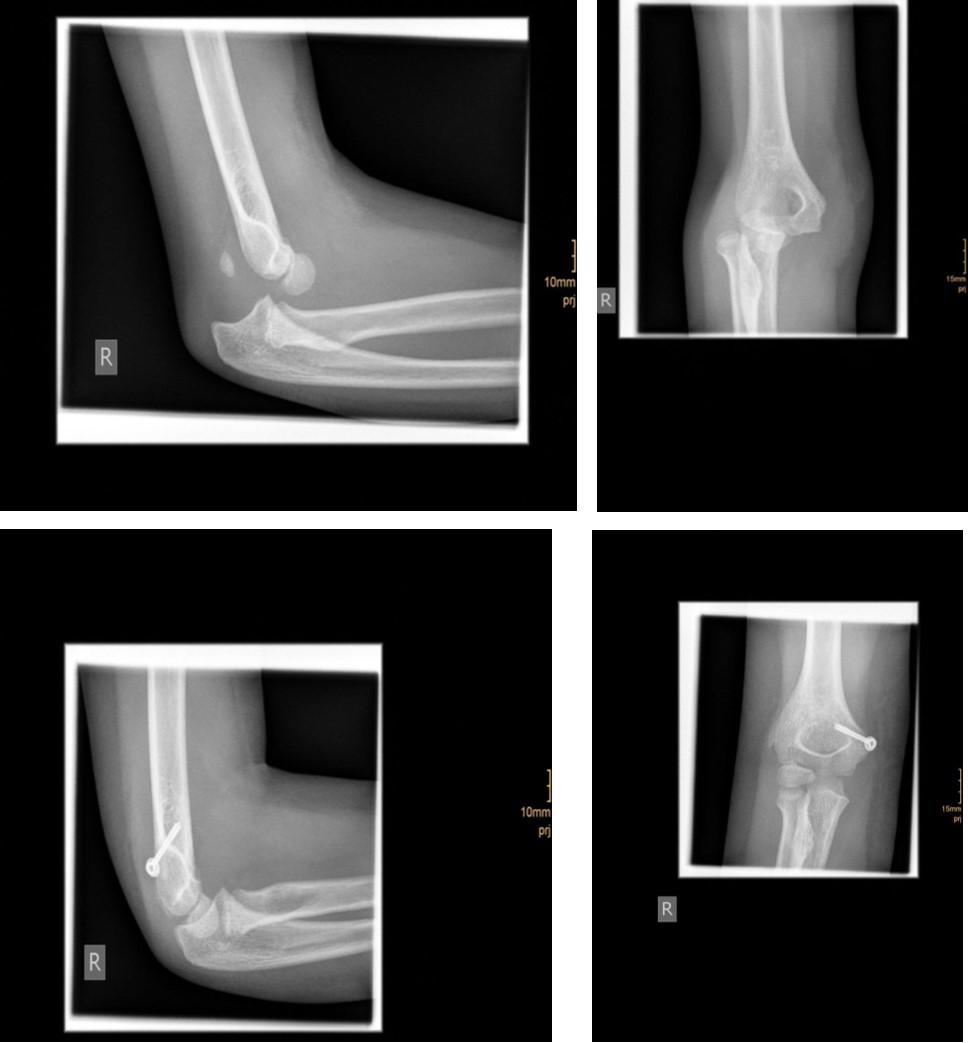

The degree of displacement may be seen on the true lateral view. In determining whether the articular hinge is intact (i.e., stage I vs. stage II), the relationship of the proximal ulna to the distal humerus is evaluated for the presence of lateral translocation. Oblique views are especially helpful in patients in whom a stage I displacement is suspected but not evident on AP and lateral views. Figure 1 and Figure 2.

Figure 1.6 year old male patient with a undislocated left lateral condyle fracture which was succesfully treated with a cast (personal collection)

6 year old male patient with a undislocated left lateral condyle fracture which was succesfully treated with a cast (personal collection)

Figure 2.6 year old male patient with a dislocated right lateral condyle fracture which was treated by open reduction and osteosynthesis with a screw and a Kirschner wire (personal collection)

6 year old male patient with a dislocated right lateral condyle fracture which was treated by open reduction and osteosynthesis with a screw and a Kirschner wire (personal collection)